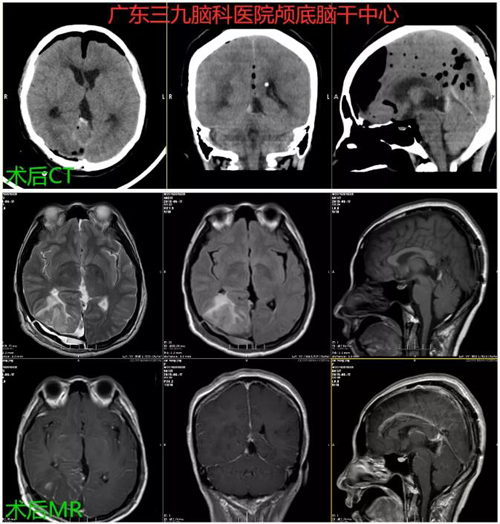

图2:术后CT及MR示:松果体肿瘤切除术后改变,原病灶已切除